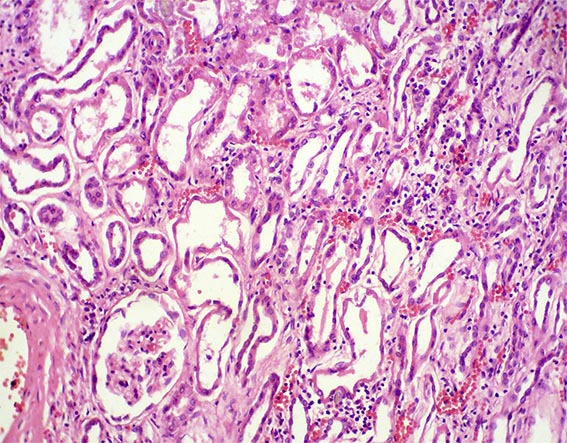

Figura 2. H&E, X200.

Figura 3.

H&E, X200.